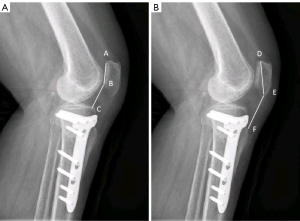

Bilateral standing anteroposterior whole-leg radiographs and anteroposterior, lateral, and axial radiographs were obtained from all patients before surgery and at the final follow-up. The whole-leg radiographs were acquired with a 14,351-inch cassette. The axial radiographs were obtained with knee flexion of 30° from the horizontal direction. As previously reported (3-5,12), measurements of the femoral tibial angle (FTA), medial proximal tibial angle (MPTA), and weight-bearing line percentage (WBLP) were obtained from whole-leg radiographs for the assessment of lower extremity alignment. FTA was measured as the angle formed by the intersection of the femoral and tibial mechanical axes. The femoral mechanical axis is the line from the center of the femoral head through the center of the knee, and the tibial mechanical axis is drawn as a line from the center of the ankle to the center of the knee (Figure 3). MPTA was the medial angle between two lines: one line of the tibial anatomical axis and a second line extending from the medial to the lateral most area of the tibial plateau, while excluding the osteophyte at the tibial plateau surface. Using a whole leg radiograph, the WBLP was calculated. The denominator was the width of the tibia as measured using a ruler, and the numerator was the tibial intersection of the weight-bearing line (with medial tibial edge at 0% and the lateral tibial edge at 100 %). Measurements of the Caton-Deschamps index (CDI) and Insall-Salvati index (ISI) were performed on a lateral view of the knee at a 30° flexion angle to assess the patellar height. Measurement of CDI and ISI were illustrated in Figure 4. Measurements of the lateral patellar tilt angle (LPTA) and lateral patellar shift (LPS) were illustrated in Figure 5. All images were imported into the same picture archiving and communications system. Measurements were made on radiographic images using standard digital tools, measuring to 0.1 accuracy (°). The image interpretation and measurements were performed by two senior readers (ML and ZL), who both had more than 10 years of experience in reading study radiographs. If readers disagreed on the measurements, readings were adjudicated by a panel of four readers (two non-author radiologists, ML and ZL).